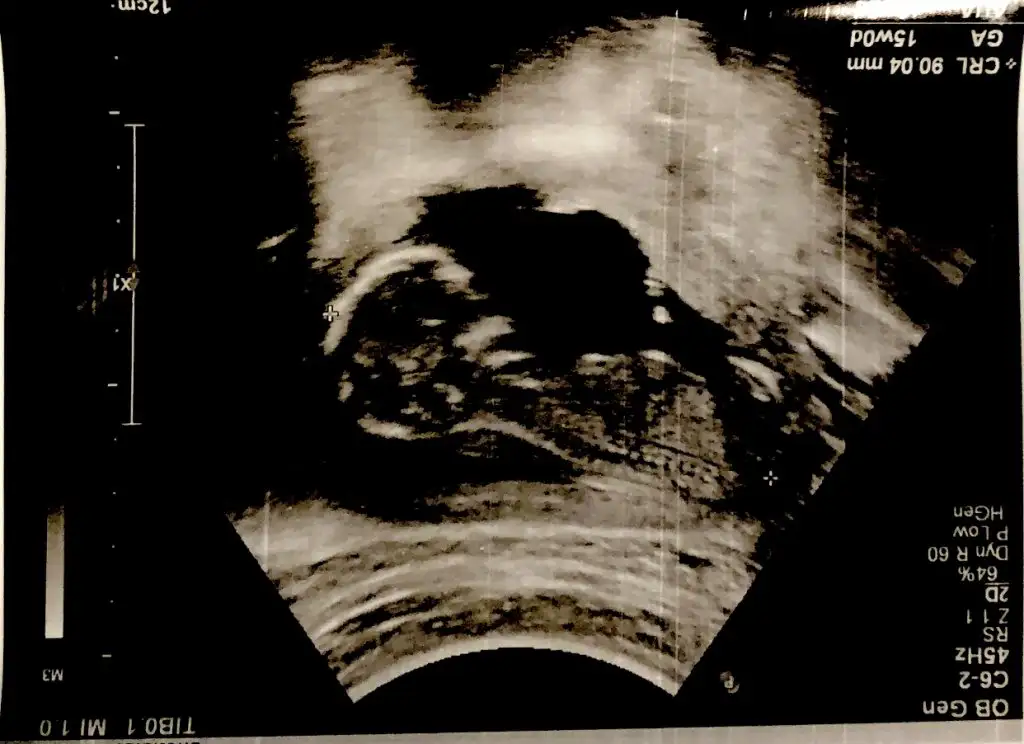

Merhaba Ikra meyra Ikra meyra 11+4te usgmize erkek gibi demiştin. Bugün kontrole gittik bebeğimiz hep poposunu döndü :) bacak arasında da kordon varmış doktor bir türlü emin olup birşey söylemedi. Usg ekliyorum pek nubu görünmüyor gibi ama belki sen görebilirsin :) sonunucu baş aşağı olduğu için onu ters çevirip ekledim. Sana bir fikir veriyor mu acaba 😌

Emin olamadım bundan canım tıp kıza benzettim 🙈